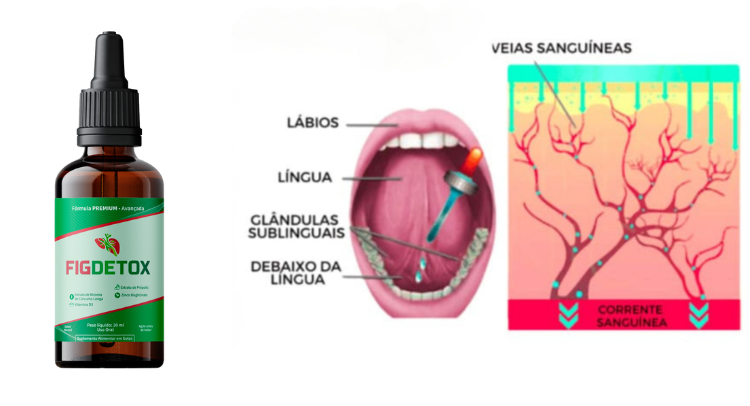

Pingue 12 gotas do FigDetox em baixo da língua e em jejum. Para melhor eficácia.

Aguarde de 10 a 15 minutos para fazer a primeira refeição ou tomar líquidos.

Tome apenas uma vez por dia, e você terá o resultados incríveis em menos de 10 dias.

A dose recomendada do FigDetox são 12 gotas por dia em jejum, uma vez ao dia.

Além disso, ele utiliza uma tecnologia sublingual exclusiva, que garante até 98% de absorção dos ativos, proporcionando resultados rápidos e visíveis. Nossos clientes já relatam melhoras significativas nos sintomas já na primeira semana!